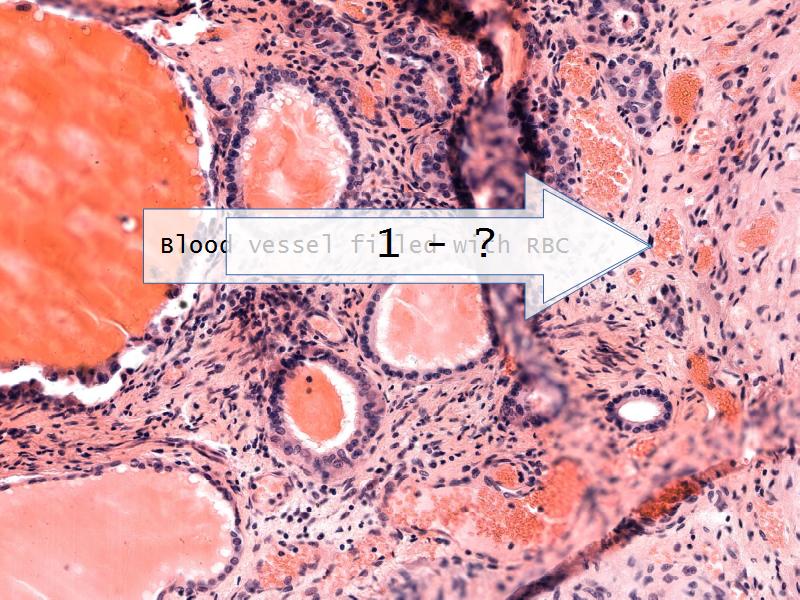

- Slide 52: Pituitary gland

Pituitary gland

How does the pituitary and hypothalamus communicate?2 ways